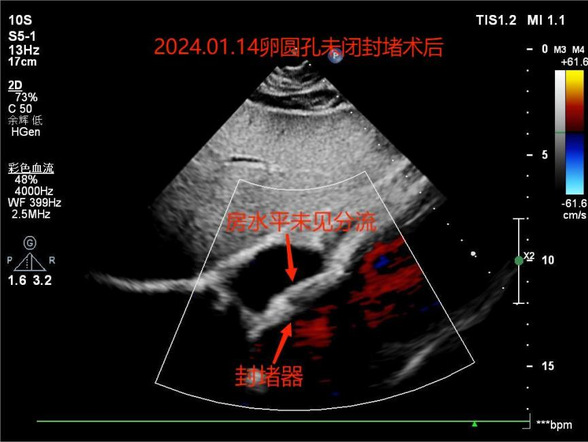

就在今年的1月11日,刘阿姨再次来到我院来解决她的“心病”,这次她被收治于心血管内科三病房进行治疗,准备行卵圆孔封堵术,关闭未能闭合的卵圆孔。术前,超声科梁笑主任为刘阿姨进行了右心声学造影,证实了心房水平大量右向左分流,符合卵圆孔未闭表现。1月14日,心血管内科三病房姜春玉主任及其团队在我院导管室为刘阿姨完成了卵圆孔未闭封堵术。手术过程约1小时,经穿刺右股静脉置入封堵伞,术中术后超声均证实封堵伞位置形态正常,二尖瓣无反流。手术很顺利,手术过程中,刘阿姨并没有感到不适,术后8小时左右,就可以下地活动了。现在,刘阿姨的“心病”已除,由卵圆孔未引起的卒中也不会再发了,她说:“悬着的心终于落地了,现在心情很美丽。”

卵圆孔未闭封堵术后超声检查